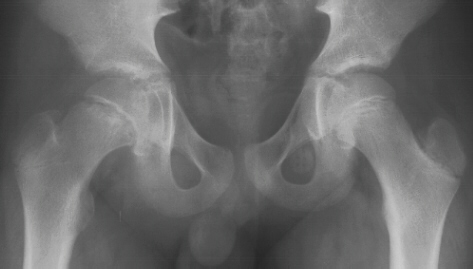

normal. At his three-month follow-up visit, the patient complained of a

two week history of vague left hip pain. AP

and frog-leg lateral radiographs revealed a grade 1 left slipped capital

femoral epiphysis. He had an in situ pinning of his left hip the next day

without complications

.